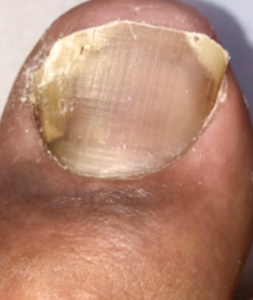

陥入爪

爪は平らだが、端が食い込んでいる

①陥入爪です。食い込んでいる爪の端だけを抜きます。

1.治療前